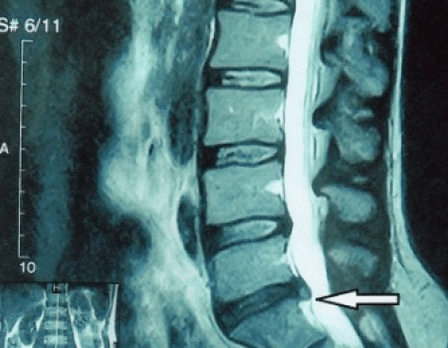

Omdat de schijven zelf alleen kunnen worden gezien met behulp van CT of MRI, zijn magnetische resonantie en röntgencomputertomografie geïndiceerd om de interne structuur van kraakbeen en formaties zoals uitsteeksels en hernia's te verduidelijken. Met behulp van deze methoden wordt dus nauwkeurig een diagnose gesteld en is het tomografieresultaat een indicatie en zelfs een actuele gids voor de chirurgische behandeling van een hernia op de afdeling neurochirurgie.